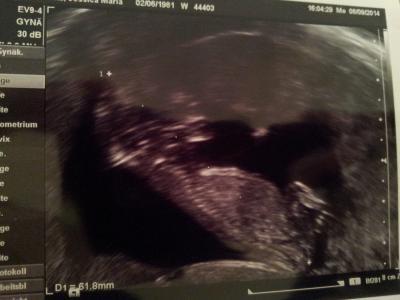

Babylein ist 6cm Ssl, zeitgerecht und ohne Auffälligkeiten :) Soll mich aber trotzdem in der Uniklinik vorstellen zur weiteren Betreuung da er noch nie eine Patientin mit meiner Krankheit hatte. Krümel hst getobt wie verrückt als würde es ihm jetzt besser gehen. Bin erleichtert. Lg Jessy